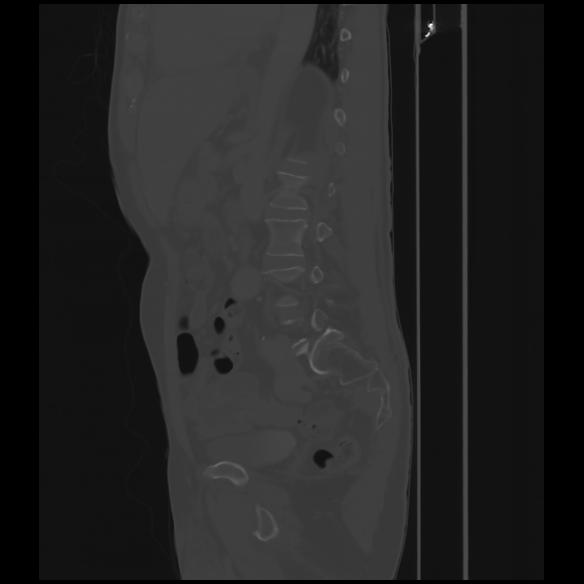

7 CUERPO,CE,Sagittal,3.000,CUERPO,Sagittal,